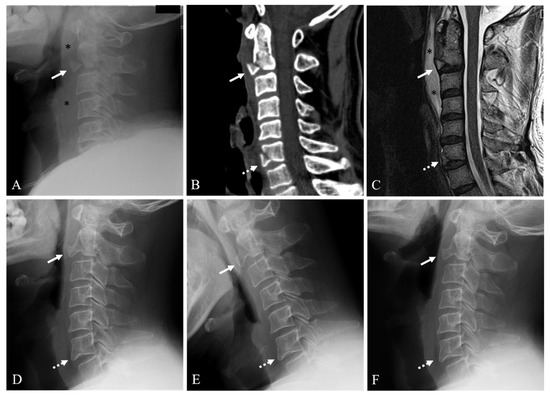

Twenty-six patients (78.8%) were in the union group (Figure 2) and seven patients (21.2%) were in the nonunion group (Figure 3). The demographic data and information for the union and nonunion groups of conservatively managed anterior C2 TD fractures are summarized in Table 1. Mean age at the time of diagnosis was not statistically different between the union and nonunion groups (51.5 years vs. 51.9 years, p = 0.961). Mean follow-up time was not statistically different between the union and nonunion groups (15.4 months vs. 12.0 months, p = 0.282). At the time of diagnosis, all patients were neurologically intact.

Figure 2. Lateral X-ray (A) and sagittal 2-dimensional (2-D) reconstructed computed tomography (CT) scan (B) showing anterior C2 tear drop (TD) fracture (white arrow), C6 fracture (dotted white arrow), and prevertebral soft tissue swelling (asterisks). Sagittal magnetic resonance imaging (C) showing anterior C2 TD fracture with 38% avulsion fracture ratio (white arrow), C6 fracture (dotted white arrow), and prevertebral hematoma (asterisks). At 12-month follow-up after Philadelphia brace, neutral (D), flexion (E), and extension (F) lateral X-rays showing solid fusion of anterior C2 TD fracture (white arrow) and C6 fracture (dotted white arrow).